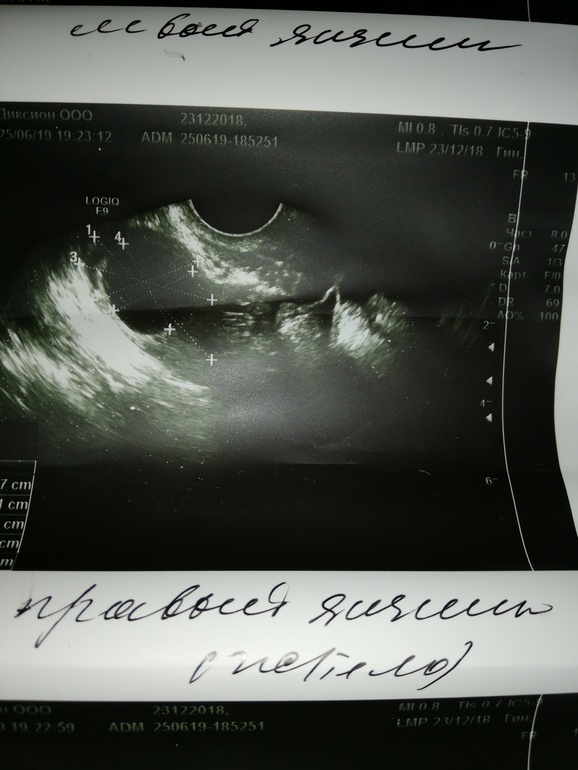

Здравствуйте девочки, это скорее крик о помощи, я просто уже не знаю что делать. Я знаю, что у кого то есть проблемы и по серьёзнее, чем моё непонятное нытье. В сентябре прошлого года была киста желтого тела, и беременность как потом выяснилось, но было прерывание. Затем кок на пол года. Сейчас первый цикл отмены, начала тестить овуляцию, где то 14,15 день увидела 2 яркие, были выделения Яб, грудь болела, тянущие боли с отдачей в задний проход, думала все, вот она. Пошла на узи 19д,сказала да, овуляция жт 23мм.я успокоилась, но начало тянуть с права, думаю дай схожу, 23 дц, и тут на тебе, то ли кжт, то ли фолликулярная. Я прикрепляю снимки. Может быть кто нибудь сталкивался с похожим, или может кто нибудь знает что именно у меня

Так я сегодня на узи спрашиваю, какая киста, она мне фолликулярная, овуляции у вас не было. А предыдущая, сказала да была.

По фото похоже на фолликул. У меня был в августе фолликул 33*21 мм, узистка сказала киста, но я через день пришла снова на УЗИ и там было ЖТ. По фото фолликул и ЖТ отличаются, у ЖТ ободок видно с неровными краями.

Вот ЖТ

А это фолликул

Ваши снимки не о чем не скажут даже врачу. На УЗИ что ЖТ что фолмкулярная киста совершенно одинаковые. Единственное как их можно отличить это наблюдать за фолликулов с 2-5 дня цикла.

А сейчас можно только гадать